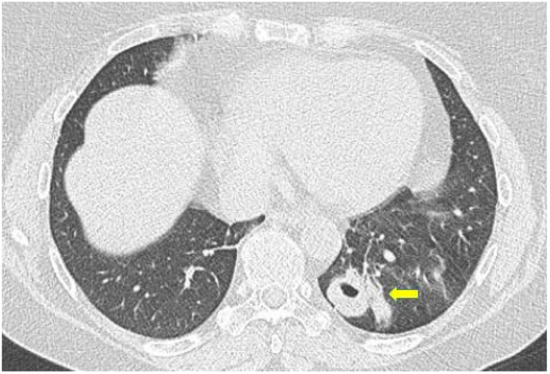

2.10. ILD in ANCA-Associated Vasculitides

2.10.2. Morphological Patterns and Imaging